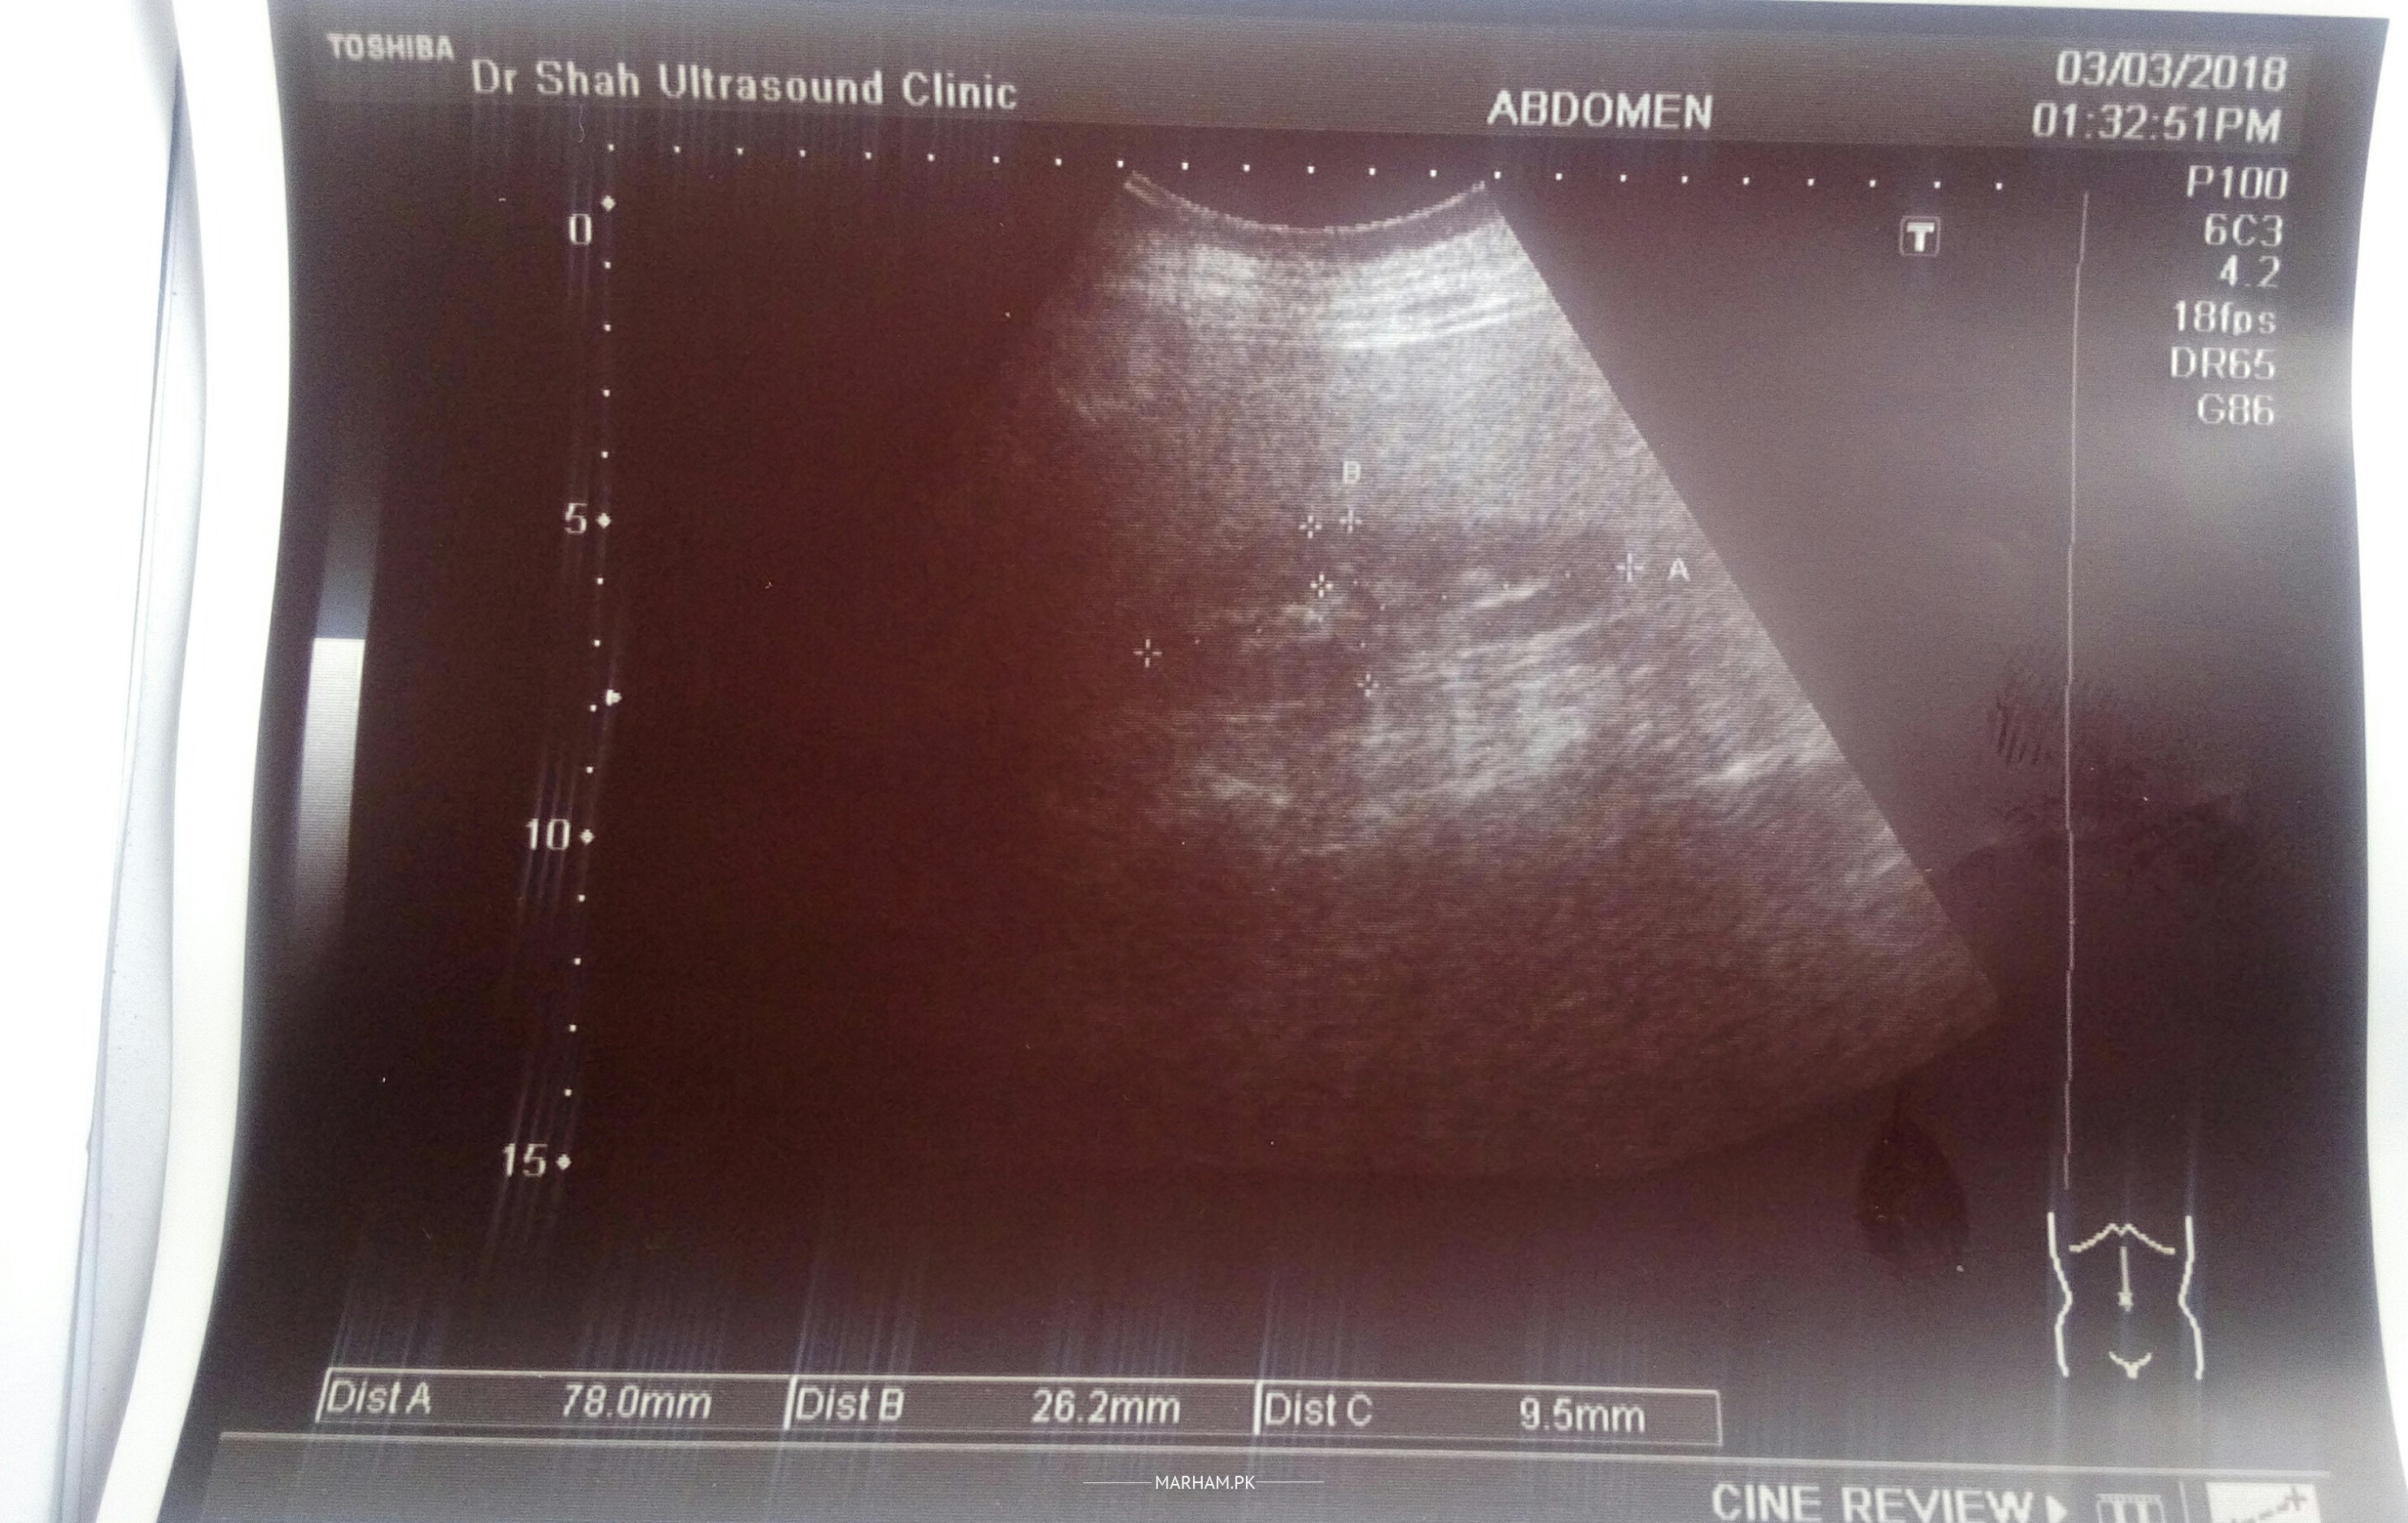

Doctors especially nephrologist . please see this ultrasound are the kidneys?about size and shape?(Rt.78x26.2x9.5mm).(left.66.7x29.7x11.1mm) size is in some one tell me?

Kidneys are relativly smaller and echogenic